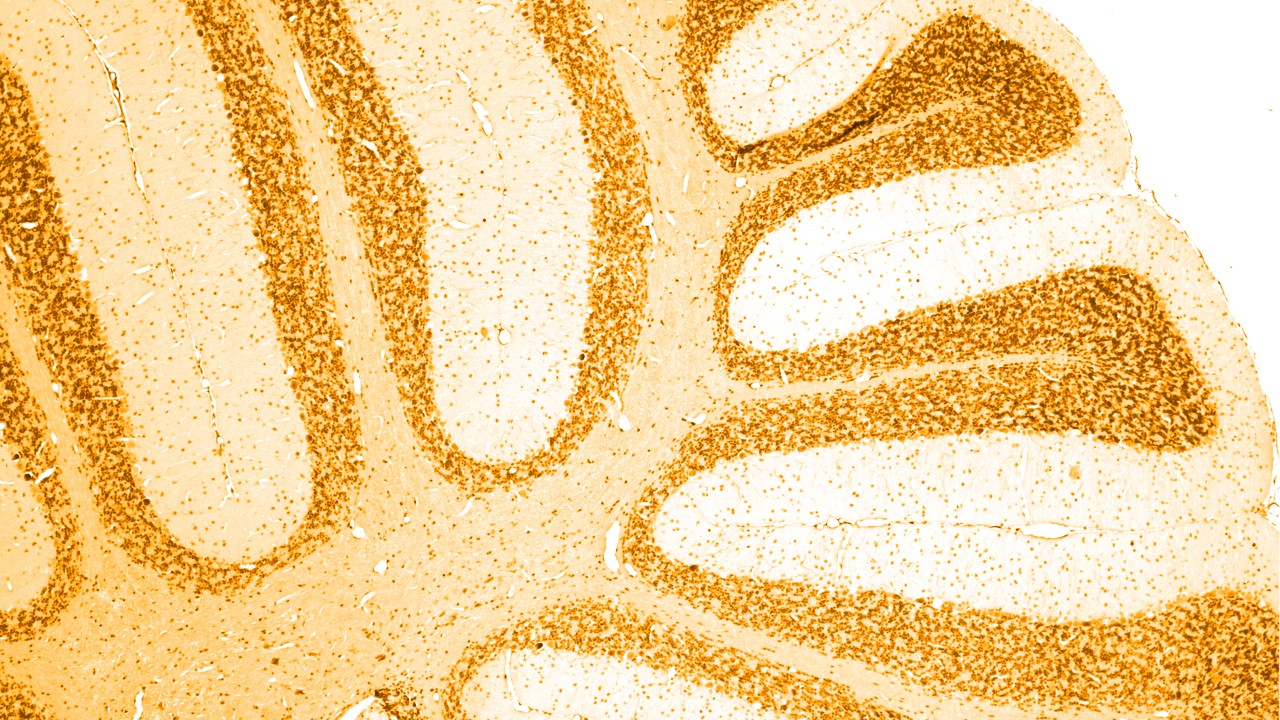

Neurologiske sygdomme er sygdomme i centralnervesystemet eller det perifere nervesystem. Med andre ord: hjernen, rygmarven, nerverne og musklerne, som regulerer og koordinerer kroppens aktiviteter.